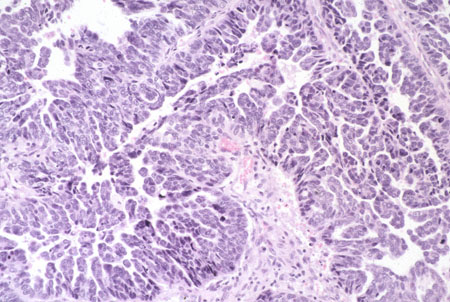

A hiperplasia complexa com atipia citológica é denominada neoplasia intraepitelial endometrial (NEI).[35][Figure caption and citation for the preceding image starts]: Neoplasia epitelial in situ crescendo em endométrio proliferativo (fotomicrografia, coloração de hematoxilina e eosina)Do acervo de George Mutter MD, Division of Women's and Perinatal Pathology, Brigham and Women's Hospital, Harvard Medical School [Citation ends].

Mutação do gene supressor de tumor PTEN: a coloração imuno-histoquímica utilizando anticorpos anti-PTEN em tecido parafinado mostra que mais da metade dos adenocarcinomas endometriais endometrioides, e das lesões precursoras de neoplasia endometrial intraepitelial (NEI), terão perdido a proteína PTEN.[47][48][Figure caption and citation for the preceding image starts]: Adenocarcinoma de baixo grau crescendo em endométrio proliferativo, coloração usando imuno-histoquímica (coloração marrom) para proteína homóloga da fosfatase e da tensina; observe as glândulas neoplásicas com coloração negativa (não marrom) (o epitélio normal geralmente com a coloração marrom)Do acervo de George Mutter MD, Division of Women's and Perinatal Pathology, Brigham and Women's Hospital, Harvard Medical School [Citation ends].

PTEN[Figure caption and citation for the preceding image starts]: Adenocarcinoma de baixo grau crescendo em endométrio proliferativo, coloração usando imuno-histoquímica (coloração marrom) para proteína homóloga da fosfatase e da tensina; observe as glândulas neoplásicas com coloração negativa (não marrom) (o epitélio normal geralmente com a coloração marrom)Do acervo de George Mutter MD, Division of Women's and Perinatal Pathology, Brigham and Women's Hospital, Harvard Medical School [Citation ends].